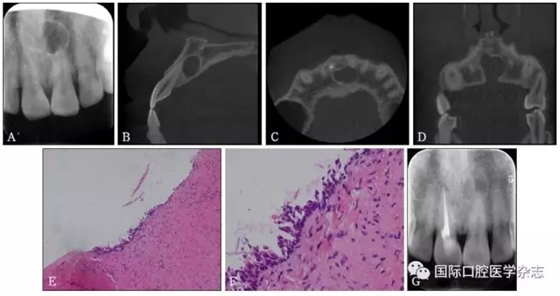

典型病例3 患者右下頜長包1月,臨床初診為44牙根尖周囊腫,治療期間反復(fù)換藥,伴右下頜脹痛,根管充填后轉(zhuǎn)診外科行根尖囊腫刮治A術(shù),術(shù)后病理示:右下頜骨KCOT伴感染(圖3)。

A:術(shù)前全景片,43—45根方透射影像,邊緣可見骨白線;B:術(shù)前充填根尖片;C、D:蘇木精-伊紅染色切片,示腫瘤襯里上皮表面為波浪狀的不全角化層,基底層細(xì)胞柵欄狀排列,細(xì)胞核遠(yuǎn)離基底膜,C圖 × 100,D圖 × 400。

圖 3 右下頜骨KCOT

Fig 3 KCOT in the rightmandible